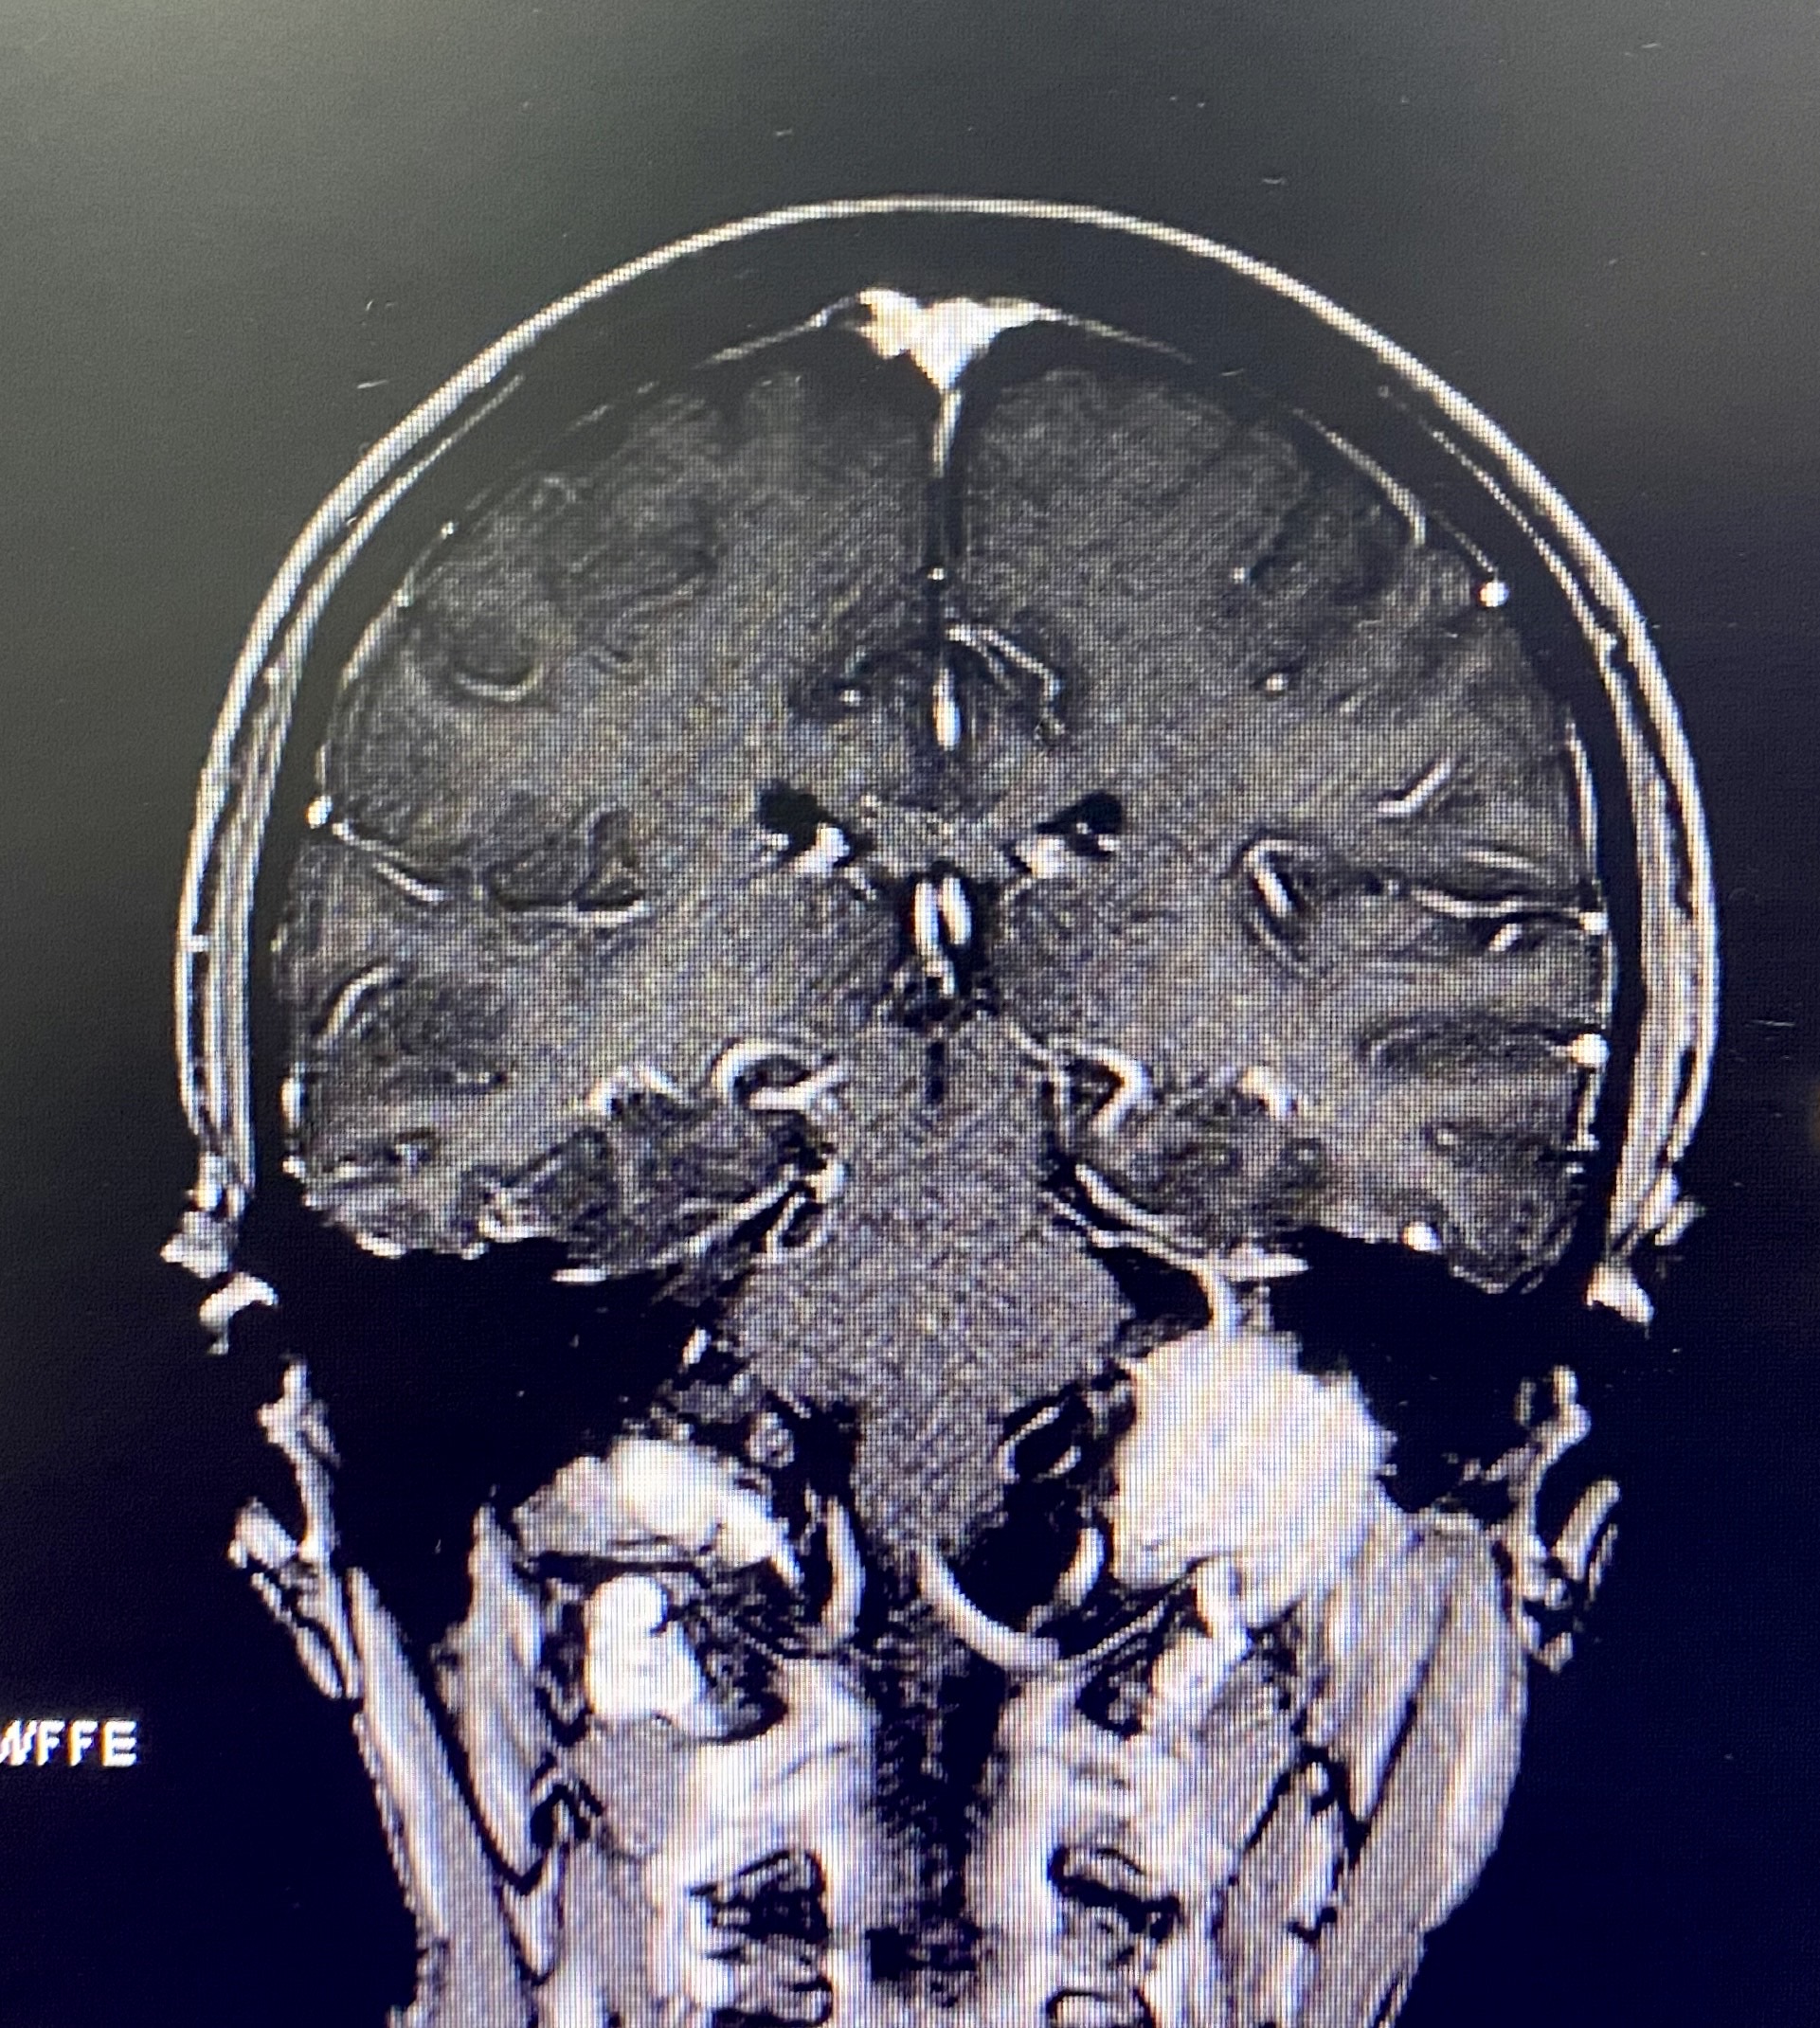

暴露面神经垂直段后可见肿瘤紧贴面神经并将其向后推挤,术中打开茎乳孔并做垂直段前移位

前移面神经后,磨除颈静脉突暴露肿瘤全程

延肿瘤边界整块分离切除肿瘤,在颈静脉孔内有多个出血的静脉孔道用明胶填塞止血。全切肿瘤后暴露完整瘤腔。